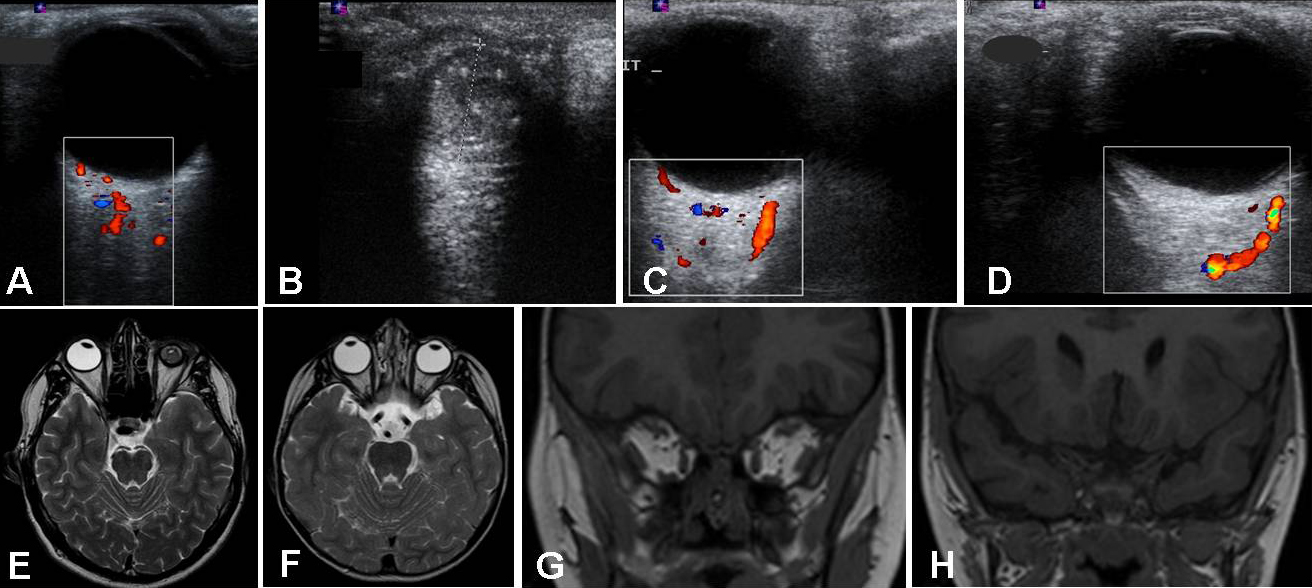

Figure 2. Ultrasound and MRI findings in III:1 and II:1. The father’s (II:1) Doppler ultrasonographic examination. This demonstrates

A: a normal right eye with the optic nerve and arteria centralis retinae; B: a left microphthalmic heterogeneous eye without the optic nerve visible. C, D: The son’s (III:1) Doppler ultrasonographic examination demonstrating the absence of both optic nerves and corresponding

vascularization, but the presence of posterior ciliary vessels (C and D for right and left eye, respectively). The vessels are represented in color. The Doppler examination is represented in the

boxes. E: II:1’s axial T2-weighted image in MRI demonstrated a normal right eye and lens and a left microphthalmic eye with thick

sclera. F: III:1’s axial T2-weighted image in MRI showed an almost normal morphology of both eyes but the absence of optic nerves (with

some remnants of dural sheath), chiasms, and tracts. G-H: Coronal T1-weighted MRI images in the midorbital (G) and intracranial (H) planes. This shows the complete lack of both orbital nerves in the son, III:1.